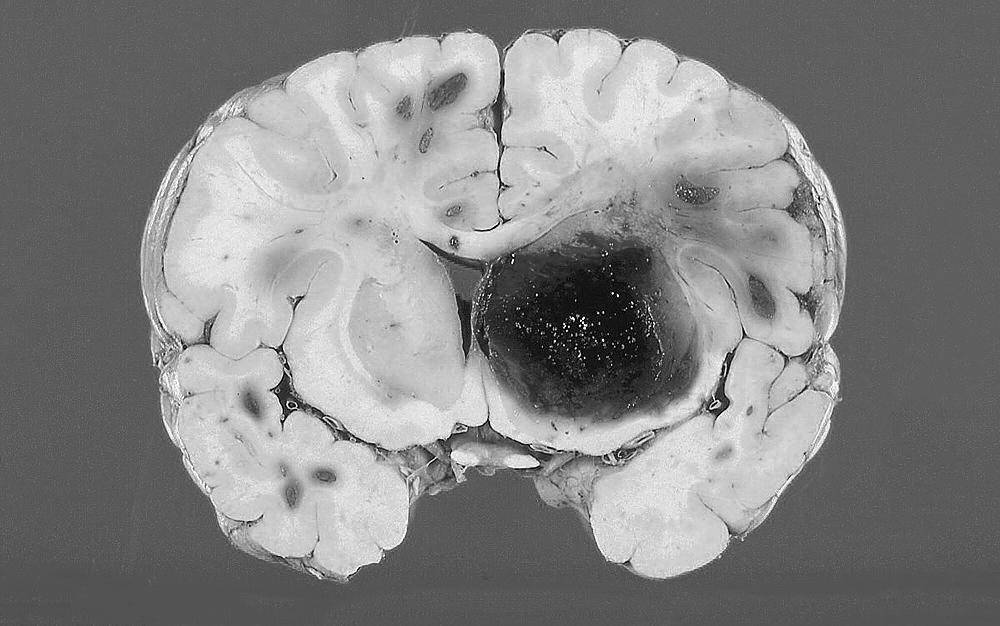

:“肯定会出毛病的,最常见就是脑出血,因为那些小血管它本来就是小的,非要它变大供应更多的血,久而久之它也会觉得累啊,然后就“自杀”--血管爆了,这个时候就不是烟雾病了,是脑出血了。”